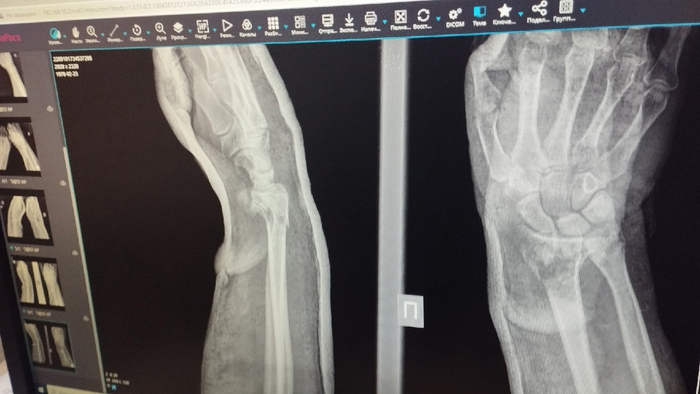

Перелом обеих рук. Их намотало на переднее колесо, и чуть не оторвало вообще.

Несколько месяцев не мог самостоятельно кушать, вытирать попу и тд...

Ближе к декабрю руки начали хоть как то функционировать.